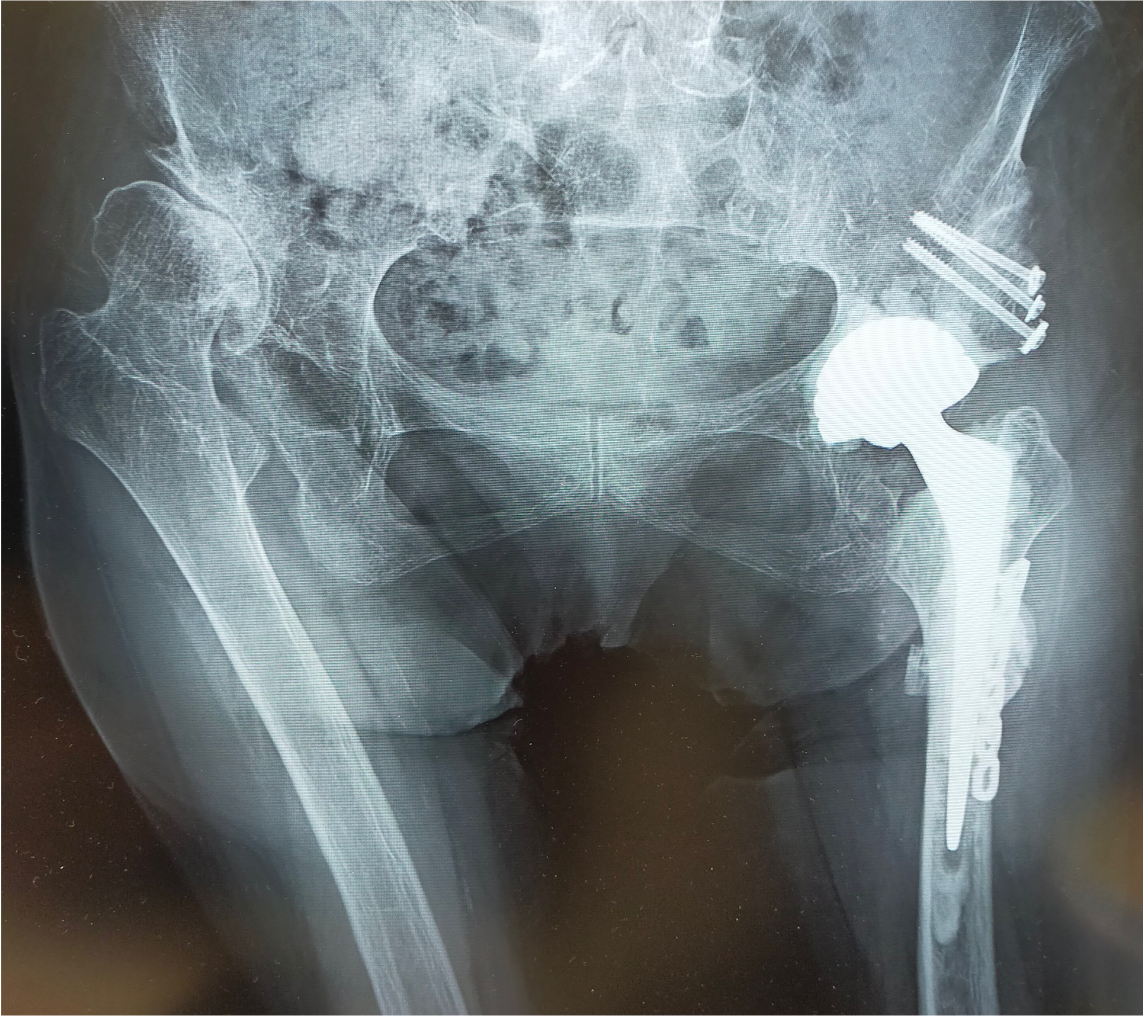

〈手術前のレントゲン〉

〈手術後のレントゲン〉(正面)

当院にて人工股関節全置換術(THA)を施行。

アプローチはAMIS(前方最小侵襲手術)で行い、翌日から歩行器での歩行訓練を開始。

術後2日目には杖なしでの歩行、術後4日目で階段昇降が可能となり、術後1週間程で退院となりました。